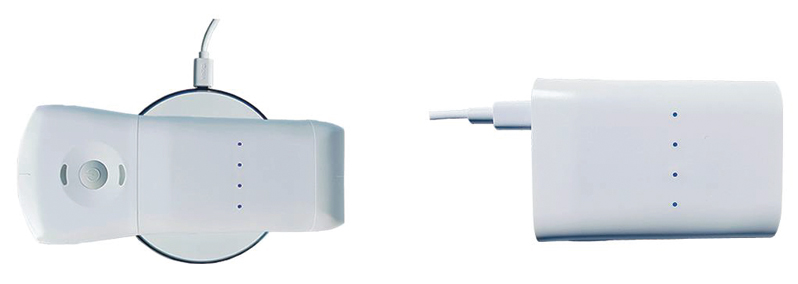

- Composed of two probes (integrating three scanning modes: Convex, linear and phased array), one macine can scan the whole body, including cardiac examination.

- Excellent temperature control design, can replace battery quickly without any too, lvery suitable for emergency clinical, hospital ward inspection, community clinical and outdoor inspect.

-REPLACEABLE BATTERIES, Tool-free quick battery replacement, Wireless charging, or battery wired charging with USB cable, You can use it anytime & anywhere.

- 64-channel hardware, presenting high-definition images.

- Work all the time without temperature rise and battery power limitation,Have a longer life.

- Scan Angle/Length: Convex 60, Linear 40mm.

- Frequency: Convex probe 3.2/5.0 MHz, linear probe 7.5/10MHz.

- Scan Mode: B, B/M, Color, PW

- Display Depth: Convex 90~300mm, Linear 20~100mm.

- Replaceable Battery: Support continuously working.

- Working System: iOS, Android

- WiFi Type: 802.11n/2.4G/5G

.Dimension:165 x71 x28mm

.Weight: 295g